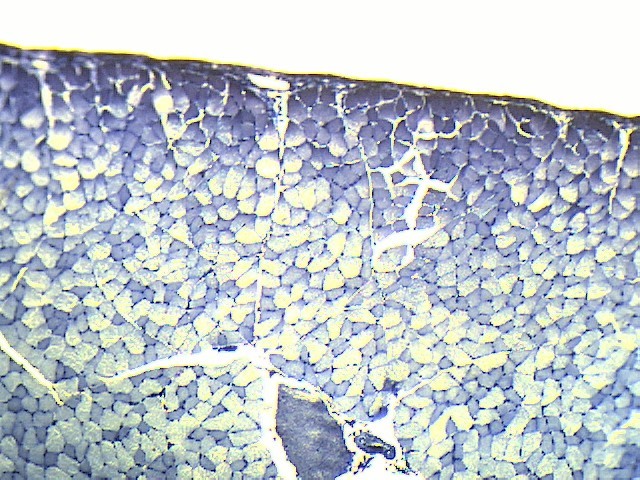

Гиалиновый хрящ - 10 шт.